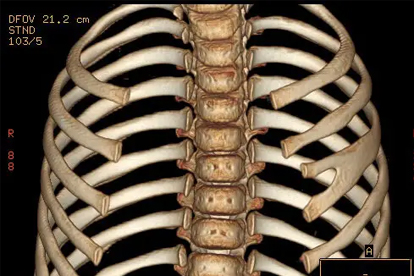

肋骨骨折常由外力撞击或骨质疏松引起,疼痛呈尖锐刺痛且随体位变化,可能伴随皮下淤血、骨擦音。需通过X线确诊,轻度骨折可佩戴肋骨固定带,遵医嘱使用洛索洛芬钠片、氨酚羟考酮片缓解疼痛。恢复期需保持呼吸道通畅,避免肺部感染。

胸膜炎多继发于肺炎、结核等疾病,疼痛随呼吸运动加重,可能伴随发热、咳嗽。需通过胸片或CT明确病因,细菌性胸膜炎可遵医嘱使用头孢呋辛酯片、左氧氟沙星片等抗生素。急性期应卧床休息,采取患侧卧位减轻疼痛。